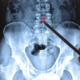

۳. رادیوگرافی اندام تحتانی

تعریف و اهمیت

اندام تحتانی (شامل ران، زانو، ساق، مچ و پا) از بخشهای بسیار مهم در سیستم حرکتی انسان است و بسیاری از آسیبها، ناهنجاریهای ارتوپدیک، تغییرات پس از جراحی در این ناحیه رخ میدهند. رادیوگرافی اندام تحتانی بهمنظور ارزیابی استخوانها، مفاصل و ساختار ضعف یا تغییر یافته بهکار میرود.

نماها و تکنیکها

- نماهای AP و lateral برای استخوان فمور، تیبیـا، فیبولا، مچ و پای پایین.

- نماهای وزنبر (weight-bearing) برای بررسی آرتروز زانو یا مچ در حین تحمل وزن بدن.

- تصویربرداری سِرتاسر پا (Full-leg) برای ارزیابی الاینمنت (alignment) اندام تحتانی از لگن تا مچ.

- در برخی موارد، نماهای مورب (oblique) جهت بررسی پیچیدهتر استخوانها.